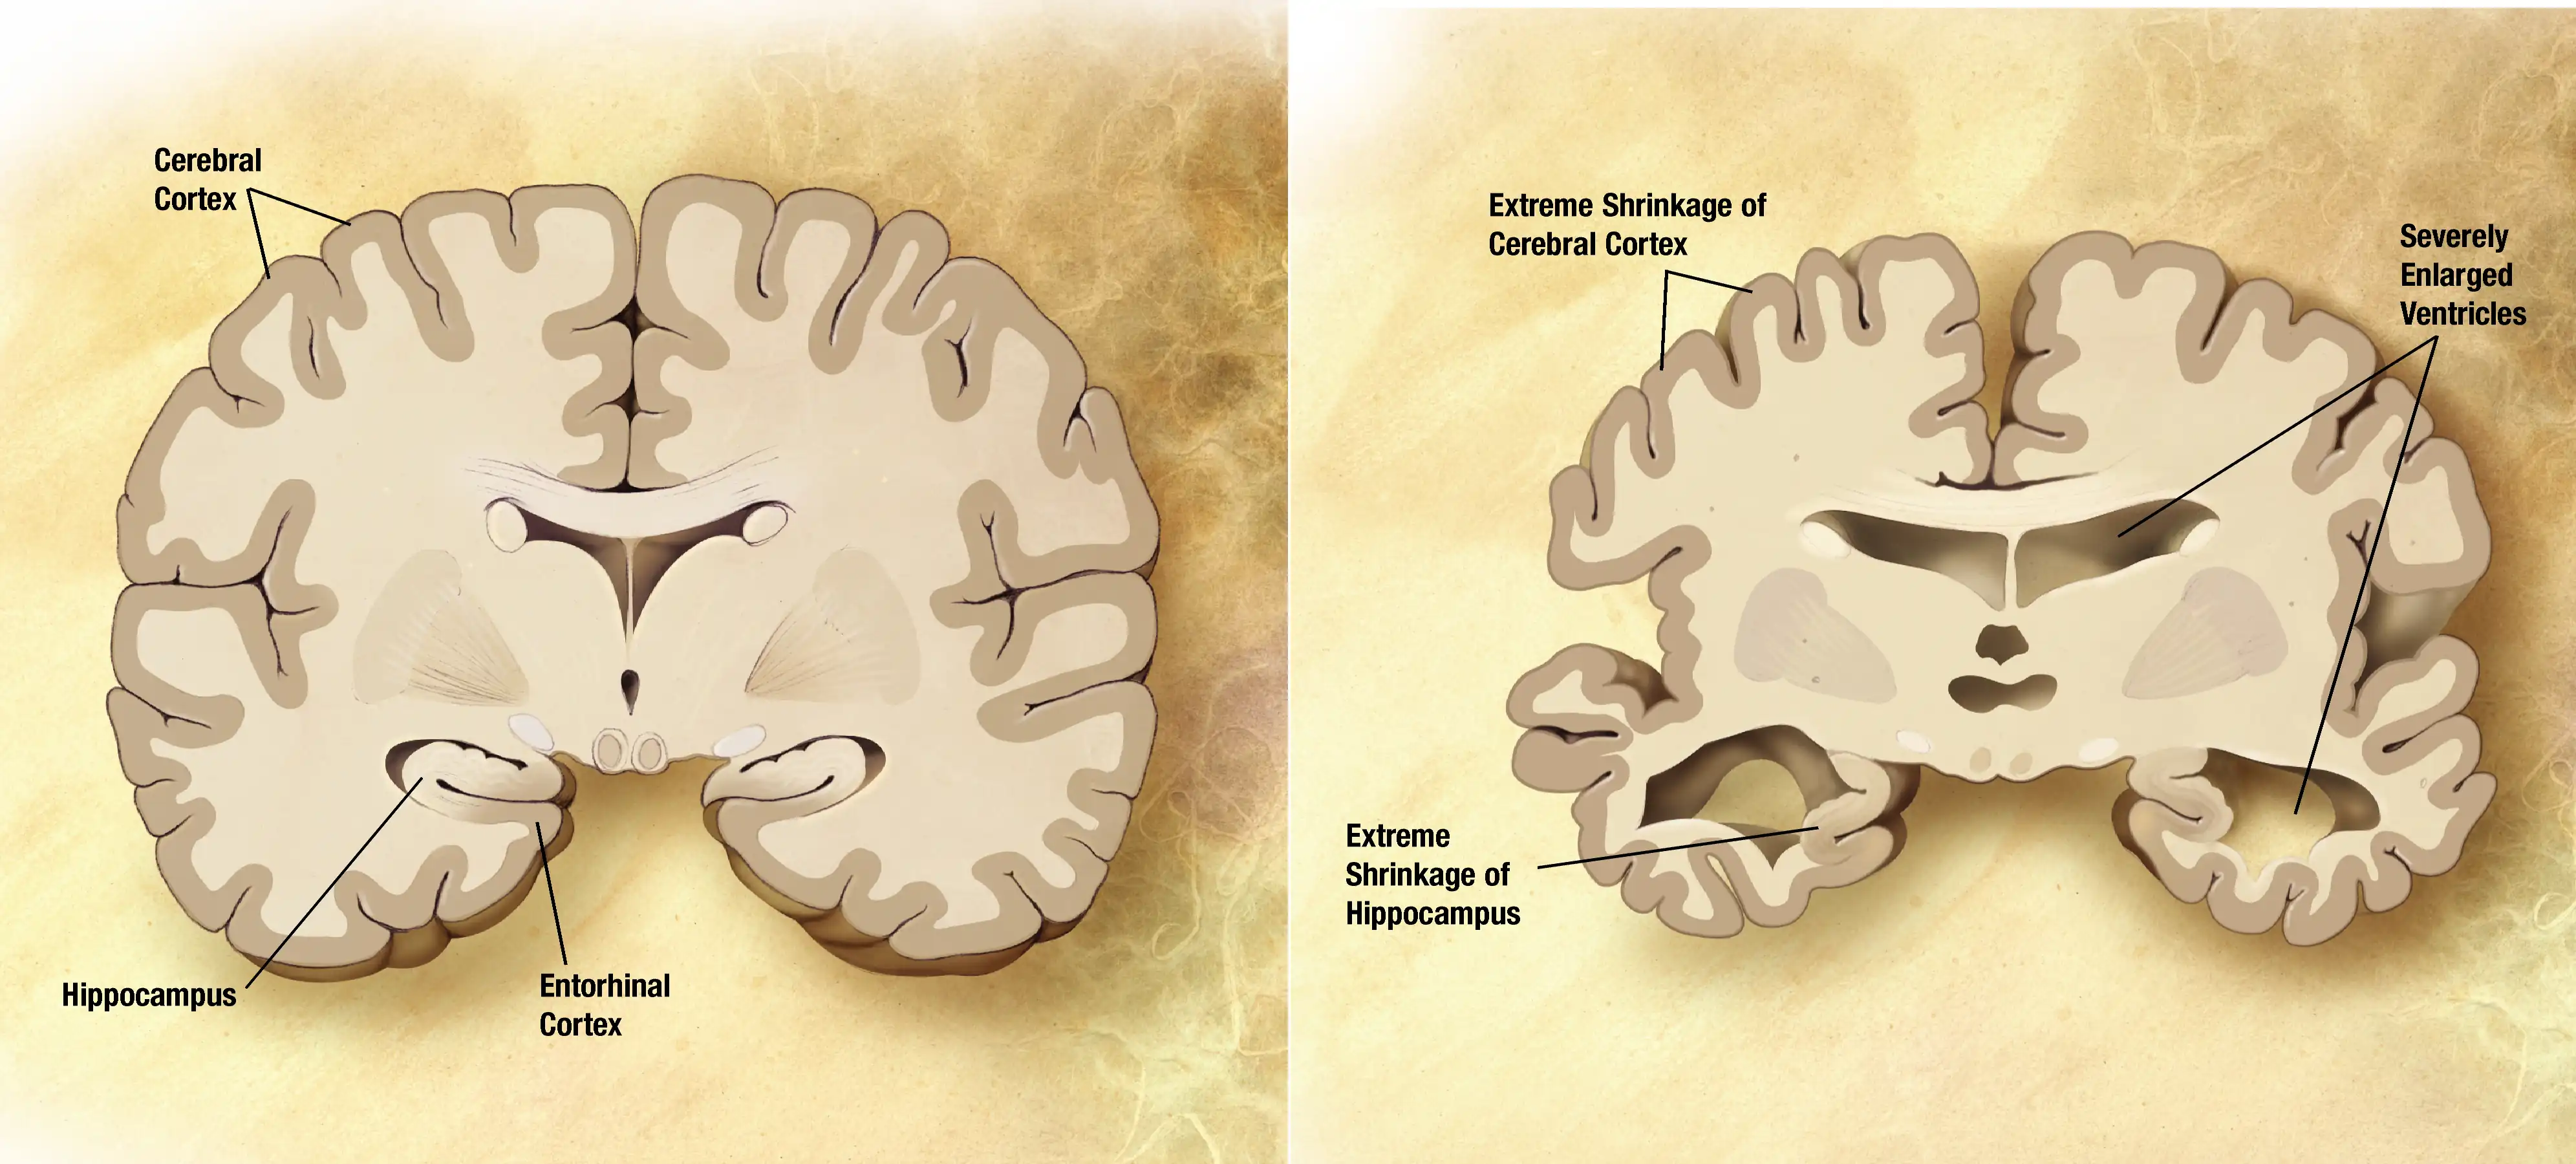

Characteristics

There are four stages of the disease:

1- Pre-dementia:

Patients will have mild cognitive difficulties. The test can help doctor to find Alzheimer's disease symbols existing eight years before diagnosis of AD. These symbols, such as short memory loss and inability to acquire new information, will cause patients cannot finish complex living activity independently.

2- Early:

Defined as first 2~3 years, patients will have difficulties with language, executive functions, perception, or execution of movements. Language problem shows obviously in decreased word fluency and shrinking vocabulary, eventually leads to general oral and written impoverishment in language. Memory losing happens as same time, but less prominent than other symbols. Alzheimer's disease doesn’t affect all memory, such as implicit memory, episodic memory and semantic memory.

3- Moderate:

Disease will eventually hinder independence; patients will lose common living abilities. On language perspective, patients are unable to recall the vocabulary, leading incorrect word substitution. Reading and writing skills are also reducing progressively. Memory problem get worse; some patients even cannot recognize close relatives. Emotion changes dramatically, leading to wandering, crying and resistance to caregiving.

4- Advanced:

This is the last stage of Alzheimer's disease. The MMSE will drop 3~4 points every year until it goes to zero. Normally, patients can still live for 8~9 years, but most patients are already lost the living ability - all of their living activities are relied on other people. Their vocabularies reduce to simple phrases; sometimes they can only speak single word. Patients will dead eventually, but the reason caused patients dead is not Alzheimer's disease - is actually some external factors, such as infection of pressure ulcers or pneumonia.